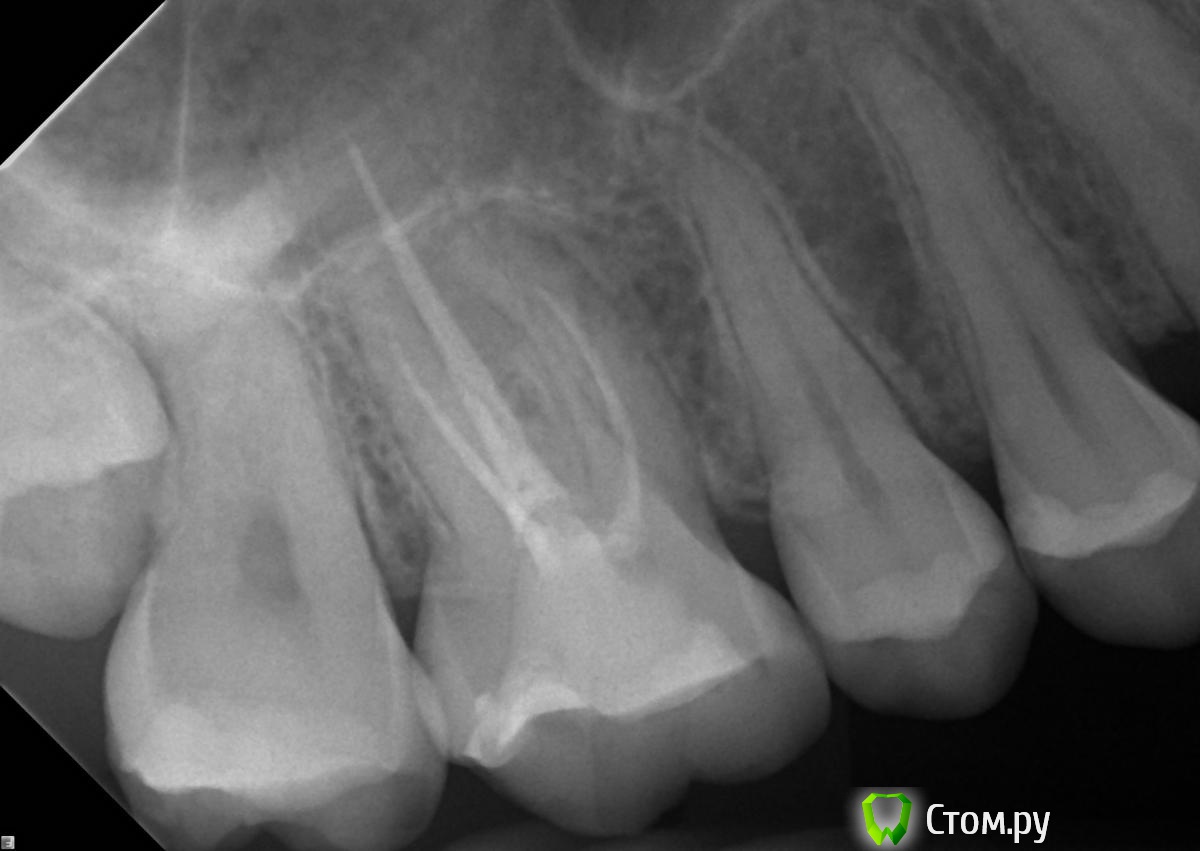

DokDent Опубликовано 30 июня, 2014 Поделиться Опубликовано 30 июня, 2014 Спасибо, менять уже поздно. Теперь приходится расхлебывать последствия. А лечил, как бы, опытный эндодонтист, который работает уже в другой клинике. Мне жаль тех, кто может попасть в его руки. Но вроде он теперь не лечит, а заведует. Как бы на работу под микроскопом непохоже. Ну если только доктор работал с завязанными глазами. Больше похоже что зуб прорезорцинили сейчас. На переднем щёчном корне уже имеются изменения,поэтому надо пытаться перелечить Ссылка на комментарий

celovek Опубликовано 30 июня, 2014 Автор Поделиться Опубликовано 30 июня, 2014 Как бы на работу под микроскопом непохоже. Ну если только доктор работал с завязанными глазами. Больше похоже что зуб прорезорцинили сейчас. На переднем щёчном корне уже имеются изменения,поэтому надо пытаться перелечить да, это отдельная история, как он там работал. Посоветуйте, пожалуйста, что делать в моей ситуации? Снова искать специалиста с микроскопом? В клинике мне сказали, что еще одно вмешательство ни к чему уже не приведет. Лучше поставить коронку, посколько в таком виде зуб находится уже почти год. Ссылка на комментарий

DokDent Опубликовано 30 июня, 2014 Поделиться Опубликовано 30 июня, 2014 да, это отдельная история, как он там работал. Посоветуйте, пожалуйста, что делать в моей ситуации? Снова искать специалиста с микроскопом? В клинике мне сказали, что еще одно вмешательство ни к чему уже не приведет. Лучше поставить коронку, посколько в таком виде зуб находится уже почти год. Да, искать эндодонтиста-профессионала с микроскопом, если расчитываете сохранить зуб надолго. И консультироваться на месте. Ссылка на комментарий

sydnik Опубликовано 30 июня, 2014 Поделиться Опубликовано 30 июня, 2014 (изменено) совет в вашем случаи только: один повторное эндолечение у грамотного спеца, которых в москве много, желательно работающего с микроскопом .Посмотрите на форуме работы врачей, свяжитесь через личку и будет вам счастье: ) Изменено 30 июня, 2014 пользователем sydnik Ссылка на комментарий

sydnik Опубликовано 30 июня, 2014 Поделиться Опубликовано 30 июня, 2014 я не букмекерская контора , чтобы давать прогнозы : )вы просили совета, что делать -вы его получили, дальше все в ваших руках.Скажу только одно: после микроскопа каналы выглядят иначе. . 3 Ссылка на комментарий

M@estro Опубликовано 1 июля, 2014 Поделиться Опубликовано 1 июля, 2014 2 Celovek. Совет номер один - успокойтесь ! И подойдите с холодной головой к поиску специалиста. В Москве их очень много,найти можно без особого труда,многие сидят на форуме. Если искать по вывеске - рискуете,впрочем- Вы на своём опыте уже всё поняли. Нужен доктор,которому Вы доверите. Человек хороший. Зуб в таком виде покрывать коронкой - нельзя. Здесь два варианта- перелечить и покрыть коронкой в итоге,либо- удаление и имплантация. Вариант -"оставить пока заболит" - не выглядит разумным. P.s. Вы спрашиваете процент , прогноз - это вопросы без ответа,тем более -"по фотографии" . Никто Вам гарантию на успех не даст. Но если Вы найдёте порядочного доктора- у него не поднимется рука с Вас повторно "срезать" деньги,не добившись результата. 2 Ссылка на комментарий